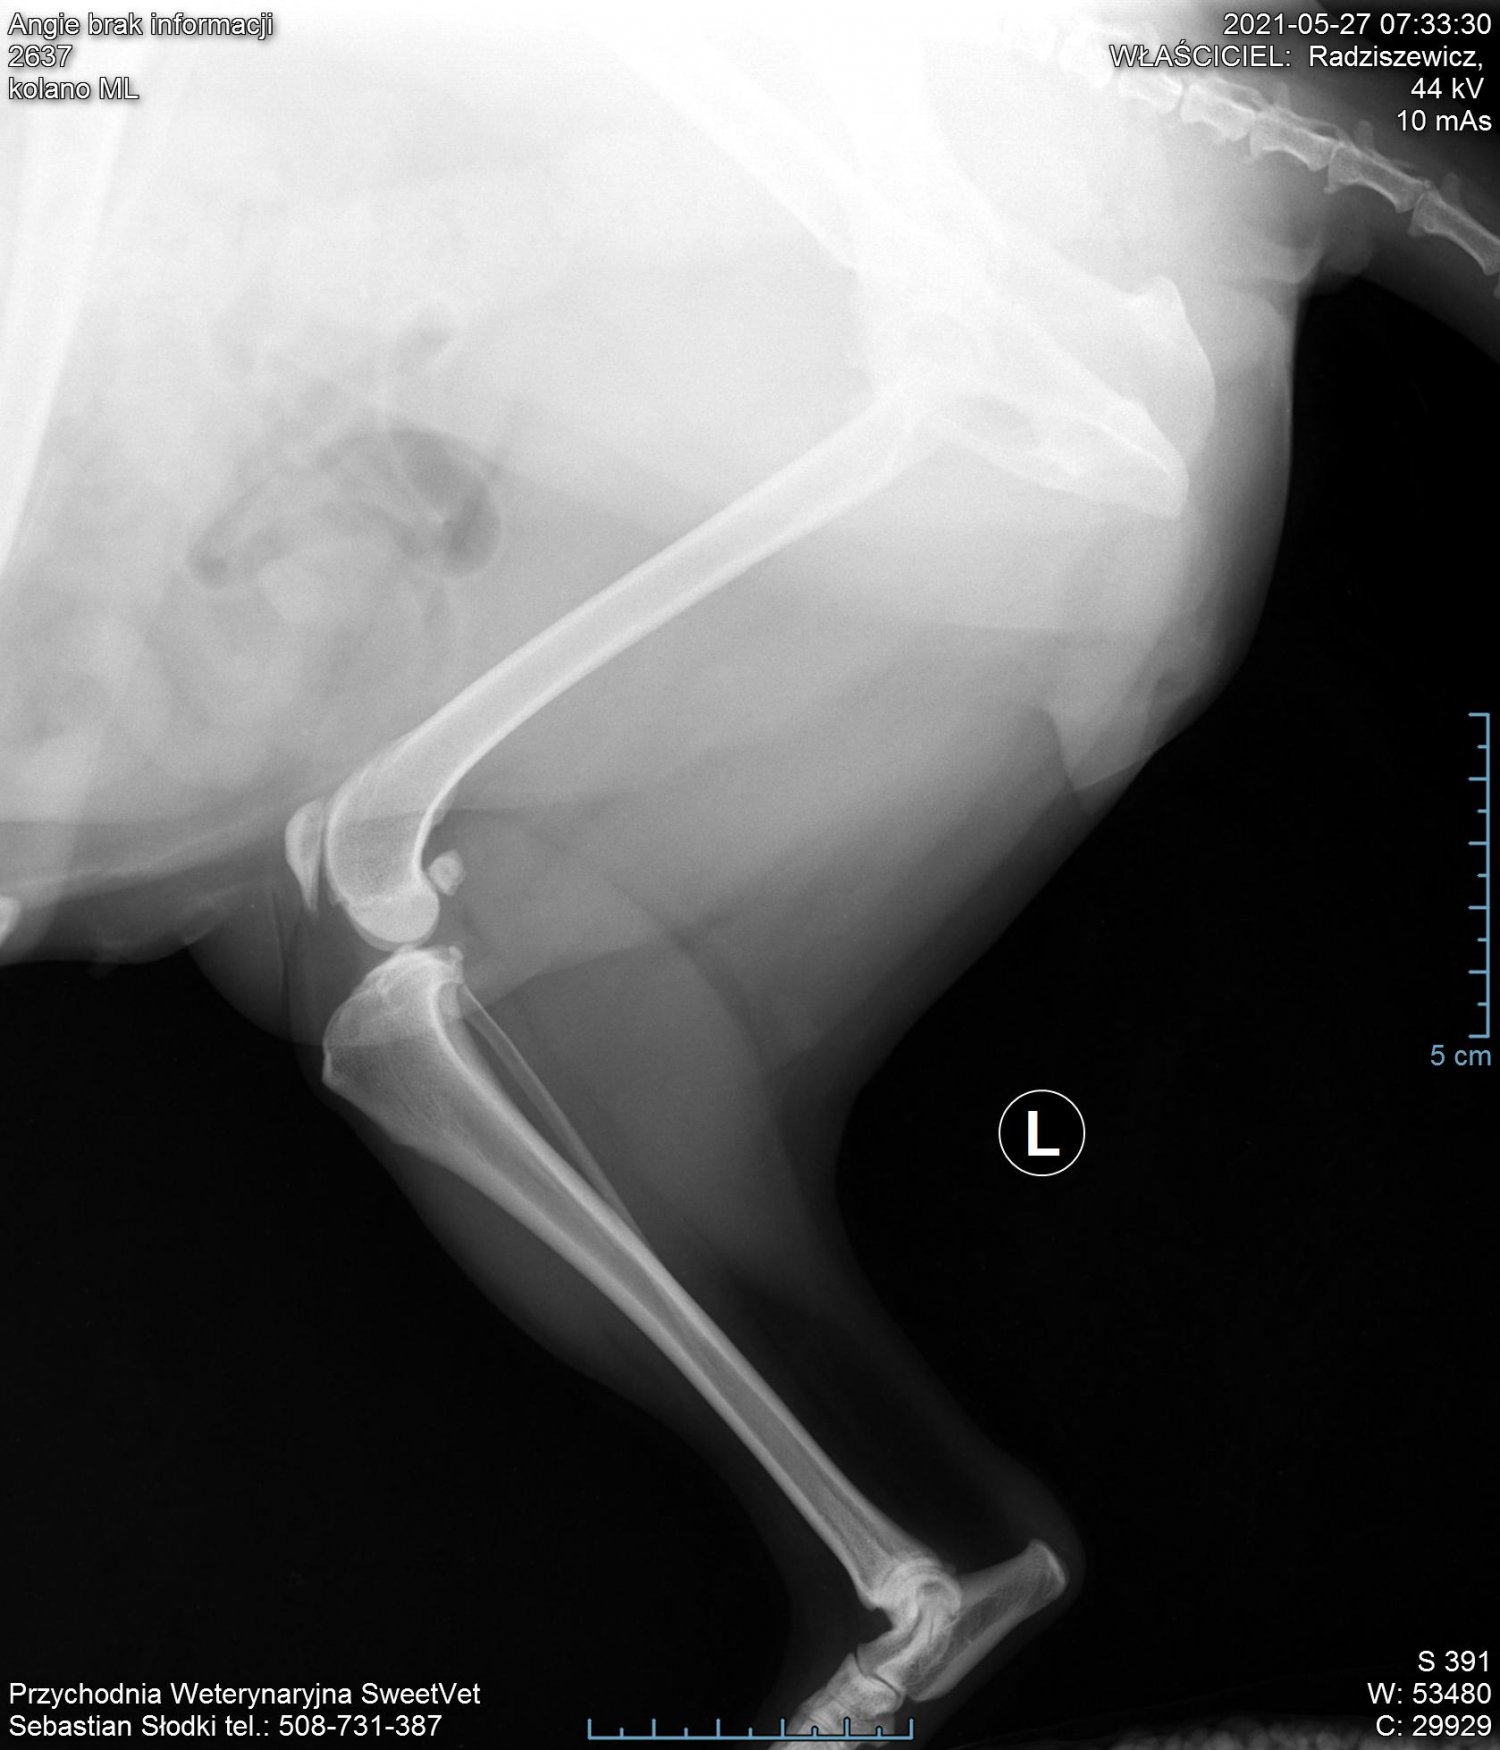

Na nasze szczęście wraz z początkiem maja dostaliśmy możliwość odbywania raz w tygodniu zajęć praktycznych na uczelni w Bydgoszczy. Jako, że mieliśmy opcję przyprowadzić na zajęcia własne zwierzęta i na nich ćwiczyć, zabrałam ze sobą moją Angie. Już na pierwszych zajęciach sunia pokazała dużą bolesność mięśni grzbietu. Tydzień później przy próbach masażu kończyn miednicznych psinka zareagowała agresywnie, od razu dała znać, że nie chce być tam dotykana. Na naszej uczelni przyjmuje fizjoterapeuta zwierząt, więc postanowiłam zaprowadzić tam swojego psa. Okazało się, że mięśnie tylnich łap i kręgosłupa są tak pospinane, że wywołują bardzo dużą bolesność. Przez odciążanie prawej (gorszej) łapki, mięśnie lewej są ciągle spięte, obolałe, przeciążone. Zaczęłyśmy działać przeciwbólowo i rozluźniająco poprzez laseroterapię, ultradźwięki i magnetoterapię. Pani zoofizjoterapeutka poleciła mi jeszcze zrobić dokładne zdjęcia RTG w jednej z bydgoskich klinik (ponieważ bez nich ciężko było wykluczyć bądź potwierdzić wskazania do zabiegu).

Nie zamierzałam się poddać i jeszcze w tym samym tygodniu pojechałam do kliniki Sweetvet na zdjęcia i konsultacje. Okazało się, że mimo tak dużej przestrzeni czasowej od wstępnej diagnozy stawy kolanowe Angie nie są w tragicznym stanie: lewa rzepka-zwichnięcie 2-ego stopnia, prawa- 3-ego. Zdjęcia RTG wykazały zwyrodnienia rzepki i głowy kości udowej w obu kończynach. Bez zabiegu sulkoplastyki i transpozycji guzowatości kości piszczelowej pogłębiające się z czasem zwyrodnienia doprowadzą do zerwania więzadeł. Doktor potwierdził, że Angie jako zdrowy pies, z dobrymi wynikami jak najbardziej nadaje się do operowania, tym bardziej, że teraz jesteśmy w stanie kolosalnie zmienić jej komfort życia.